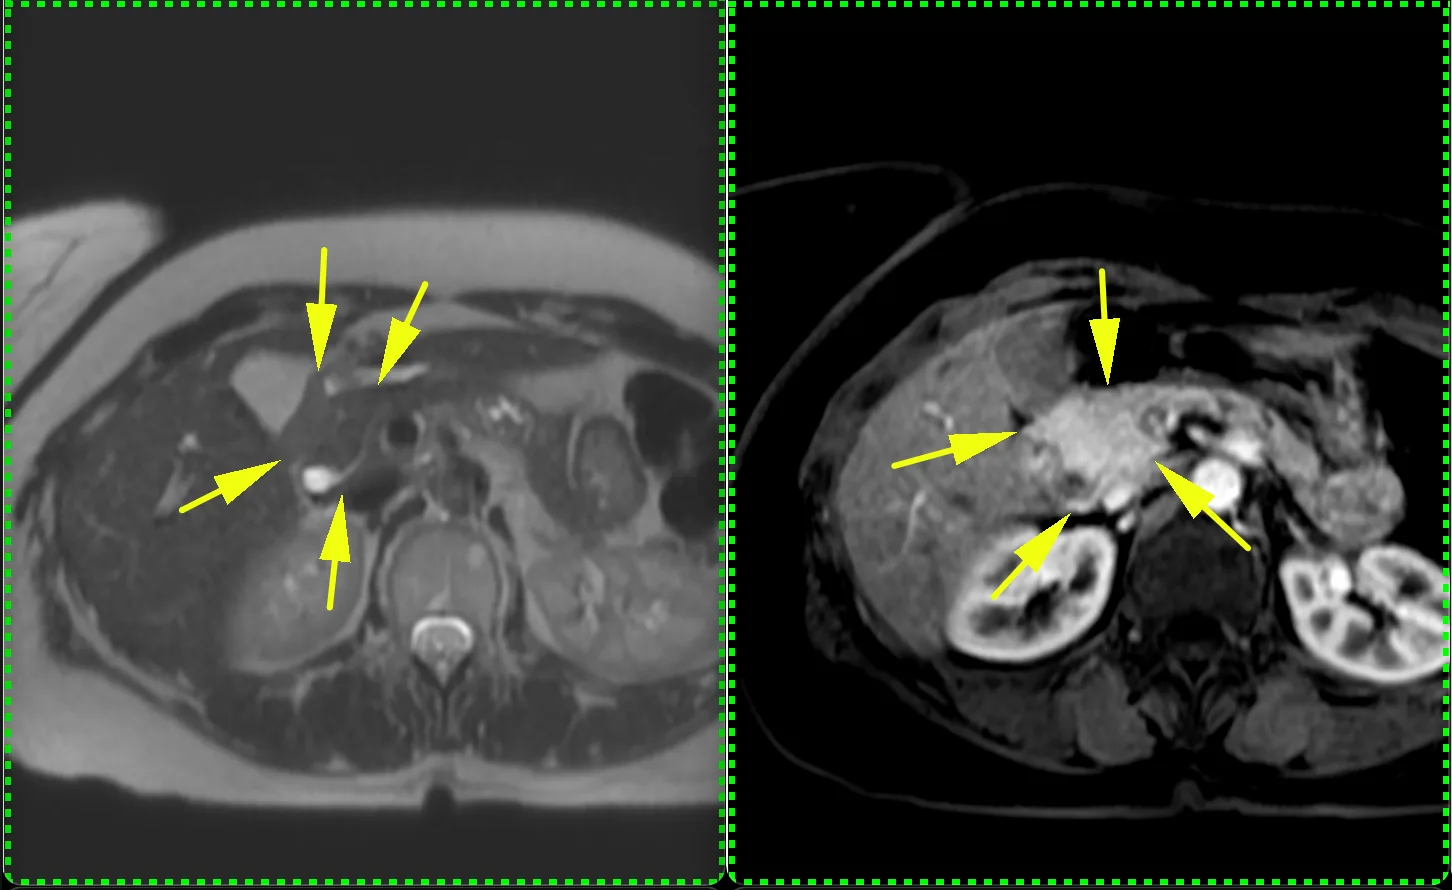

ЖЕНЩИНА 38 лет, фокальное изменение печени выявлено на УЗИ.

Повторные #КТ (с разницей в 2,5 месяца) без динамики. Имеется медленное, постепенное, слабоинтенсивное накопление контраста от периферии к центру.

На #МРТ - очень высокий сигнал на Т2, низкий на Т1, «лучистые» контуры. Истинное ограничение диффузии (ADC=460±109х10-6 кв.мм/с). Накопление контраста такое же, но на МРТ лучше видны краевое узелков накопление в артериальную фазу, тотального контрастирования нет даже на отсроченной фазе (через 5 минут).

Картина характерна: это гиалинизированная/ #склерозированнаягемангиома. Характерное стяжение контура является свидетельством склерозирования: уменьшения объёма, «рубцевания».

Гемангиомы с суженными кавернозными пространствами из-за склероза имеют большее количество более толстых и неровных перегородок, которые могут препятствовать диффузии молекул, что приводит к снижению значений ADC.

Склерозированные гемангиомы печени — это редкие доброкачественные поражения, которые часто трудно отличить от злокачественных, ибо они не имеют типичных для кавернозных гемангиом признаков.

Но! Часть признаков все равно сохраняются:

1. Значительный гиперсигнал на т2

2. Резкие, хоть и неровные, контуры

3. Центрипетальное, и иногда с приставочными узелками накопления контраста на артериальной фазе, контрастирование, пусть и неполное.

4. Стабильность в динамике